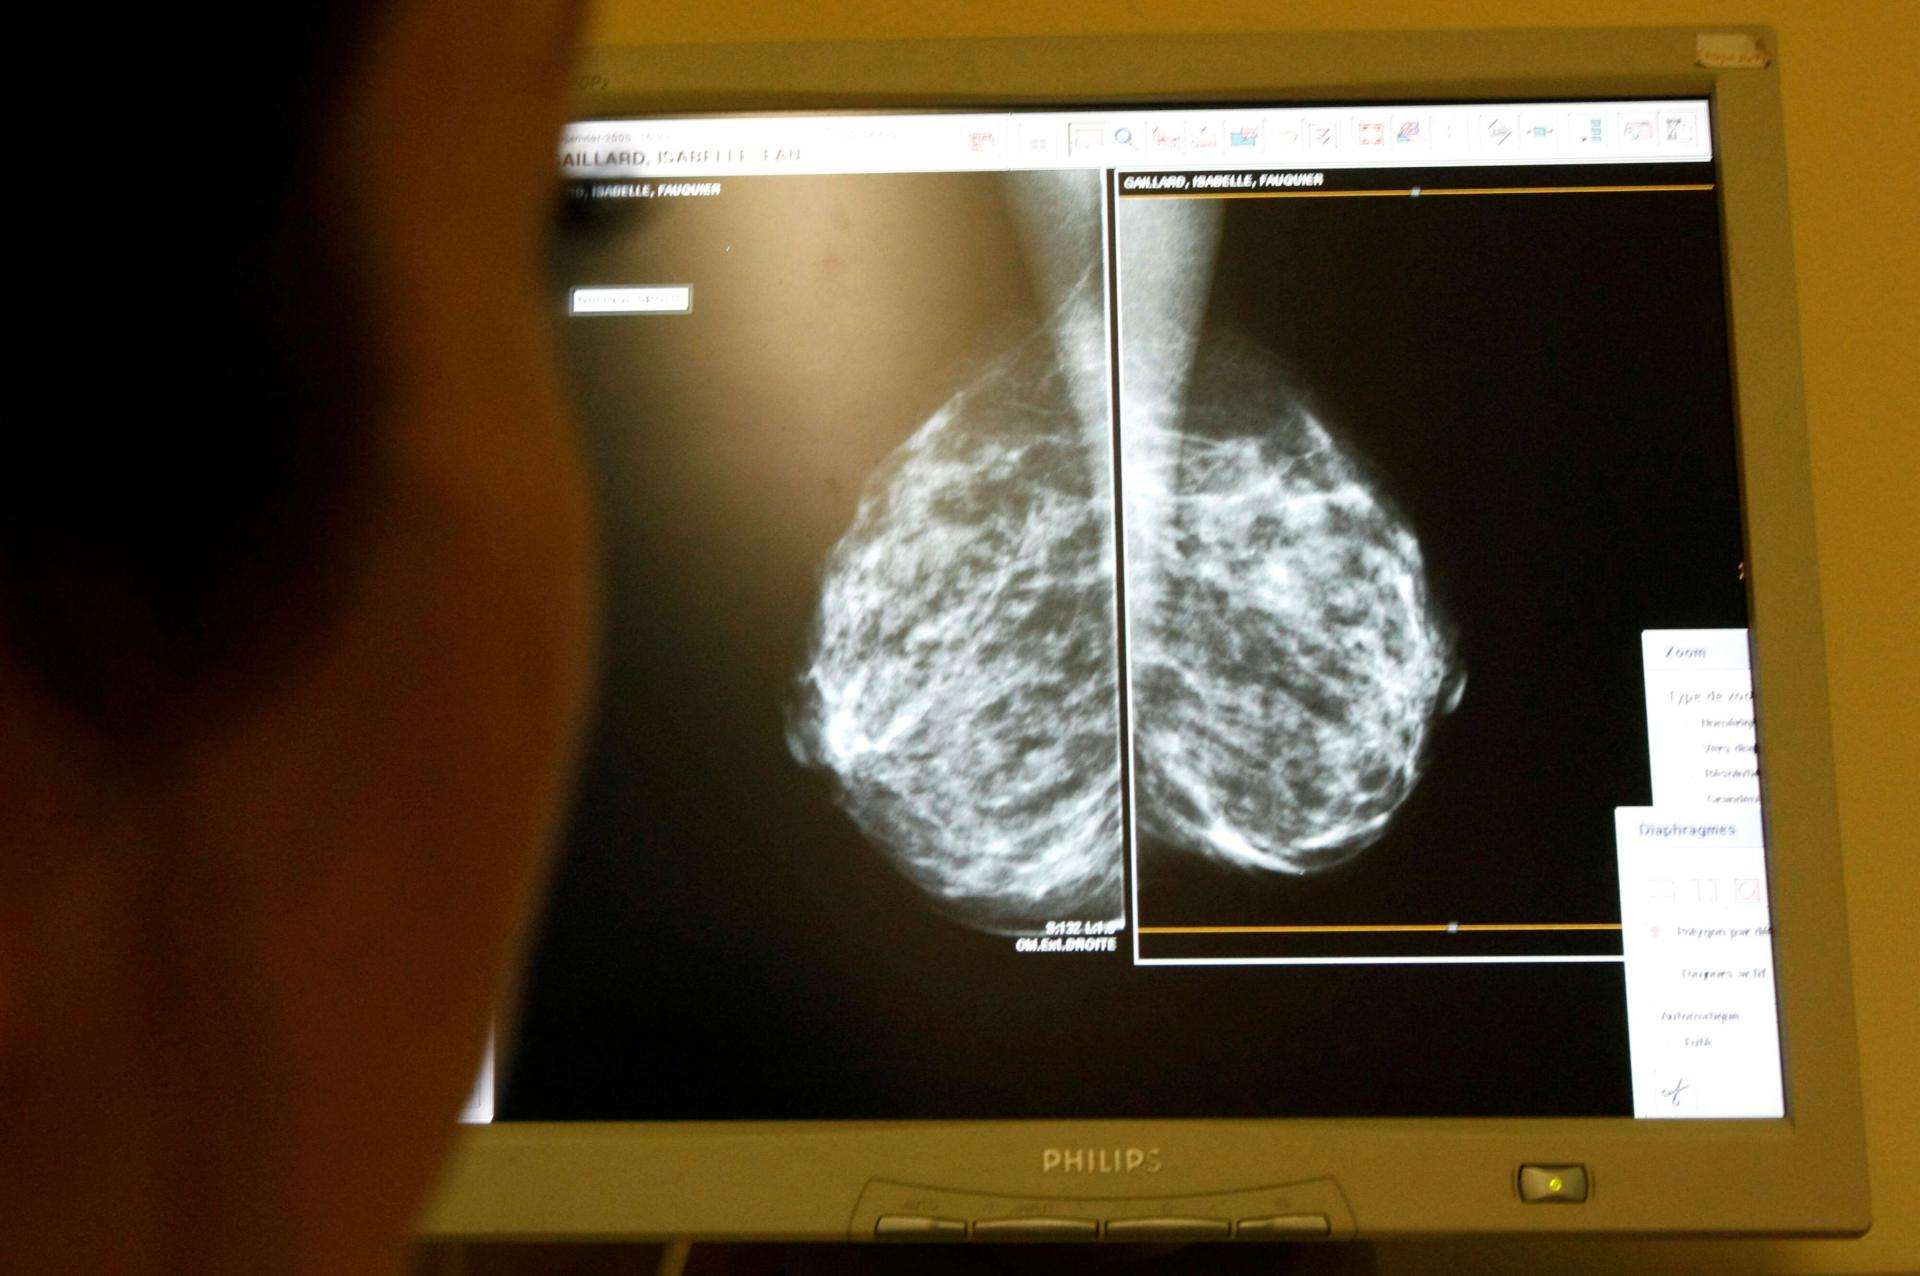

وعاين باحثون في المعهد الفدرالي السويسري للتكنولوجيا في زيورخ "إي.تي.إتش"، 30 مصابة بسرطان الثدي في الدراسة التي نشرت في مجلة "نيتشر" وعززت نتائجها تجارب على الفئران.

ويعتبر سرطان الثدي من أكثر أنواع السرطان شيوعاً حيث يصاب به نحو 3.2 مليون شخص سنوياً في العالم، بحسب بيانات منظمة الصحة العالمية، وتتزايد فرص شفاء مرضى سرطان الثدي إذا ما تم اكتشاف المرض مبكراً.